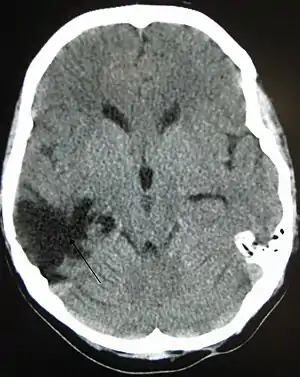

| A CT of the head years after a traumatic brain injury showing an empty space where the damage occurred, marked by the arrow |

There are several imaging techniques that can aid in diagnosing and assessing the extent of brain damage, such as computed tomography (CT) scan, magnetic resonance imaging (MRI), diffusion tensor imaging (DTI) magnetic resonance spectroscopy (MRS), positron emission tomography (PET), and single-photon emission tomography (SPECT). CT scans and MRI are the two techniques widely used and are most effective. CT scans can show brain bleeds, fractures of the skull, fluid build up in the brain that will lead to increased cranial pressure. MRI is able to better to detect smaller injuries, detect damage within the brain, diffuse axonal injury, injuries to the brainstem, posterior fossa, and subtemporal and subfrontal regions. However, patients with pacemakers, metallic implants, or other metal within their bodies are unable to have an MRI done. Typically the other imaging techniques are not used in a clinical setting because of the cost, lack of availability.[38]